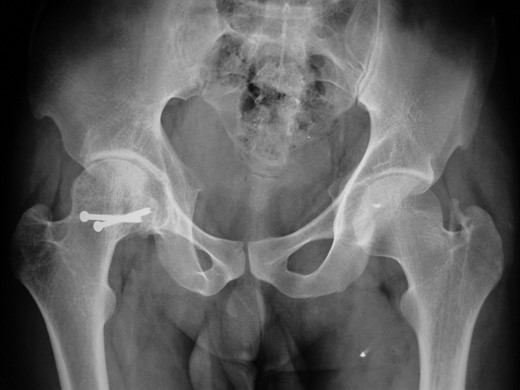

Blood parameters were within normal limits. X-ray of the pelvis revealed a right posterior hip dislocation with Pipkins's type II fracture (Rt) and ipsilateral distal medial condylar fracture with a fracture shaft of femur (Lt) (Figs 1 and 2). A CT scan confirmed the infrafoveal right-sided Pipkin's-II fracture of the femoral head (Fig. 3). A nerve conduction velocity study of lower limb suggested neuropraxia of sciatic nerve. Following attempt of closed reduction, CT scan and X-rays revealed incongruous reduction.

Initial X-ray: left thigh (anteroposterior view) and right knee (oblique view).